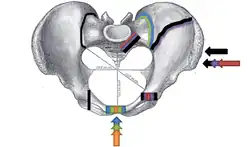

Размеры таза (в скобках у мужчин)[2]:

- Distantia interspinosa — между верхними передними подвздошными остями — 23-25 (21-23) см

- Conjugata anatomica или diameter recta (анатомическая конъюгата/прямой диаметр верхней апертуры) — между мысом крестца и верхним краем лобкового симфиза — 11,5 (10,8) см

- Diameter transversa (поперечный диаметр верхней апертуры) — наиболее отдалённое между пограничными линиями — 13,5 (12,8) см

- Diameter obliqua (косой диаметр) — между расположенными с противоположных сторон крестцово-подвздошным суставом и подвздошно-лобковым возвышением — 12,0-12,6 (12,0-12,2) см

- Прямой размер таза — между стыком II и III крестцовых позвонков и задней частью середины лобкового симфиза — 12,2 (10,8) см

- Поперечный размер таза — между центрами вертлюжных впадин — 11,5 (10,8)

- Прямой диаметр нижней апертуры — между вершиной копчика и нижним краем лобкового симфиза — 9,5 (7,5)

- Поперечный диаметр нижней апертуры — между седалищными буграми — 10,8 (8,1) см

- Угол наклона таза - угол между горизонтальной плоскостью и плоскостью верхней апертуры таза

Акушерские размеры женского таза

В гинекологии и акушерстве, кроме упомянутых, имеют значение ещё следующие размеры таза[2]:

- Distantia intercristalis — между подвздошными гребнями тазовых костей — 25-27 см

- Distantia intertrochanterica — между большими вертелами бедренных костей — 28-29 см

- Conjugata vera (истинная гинекологическая конъюгата) — между мысом крестца и самой задней точкой лобкового симфиза — 10,5-11,0 см

- Conjugata diagonalis (диагональная конъюгата) — между мысом крестца и нижним краем лобкового симфиза — 12,5-13,0 см.